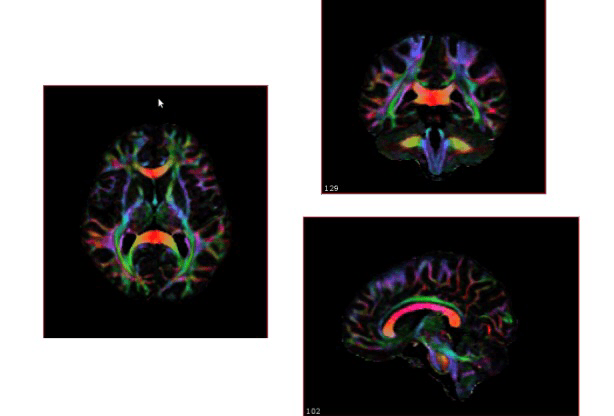

I went to the NIH and all I got was this amazing photo of my brain!

My pretty cool looking “normal brain”

I got another batch of information back from my week at the National Institutes of Health, and I really think my favorite quote ever was “patient has a normal brain”… good to know!

And lastly, the awesome nurse coordinator for the study (truly a sanity-saver!) sent me these amazing colored views of my brain from my MRI! I think the coolest part is that this was done without dye or anything… no idea what it means, but it’s pretty!

After lunch I had my second MRI, where they did something fancy and added color to it (no IV or anything for me, just computers!). Cassius was unimpressed with MRI attire – guess I smelled weird!